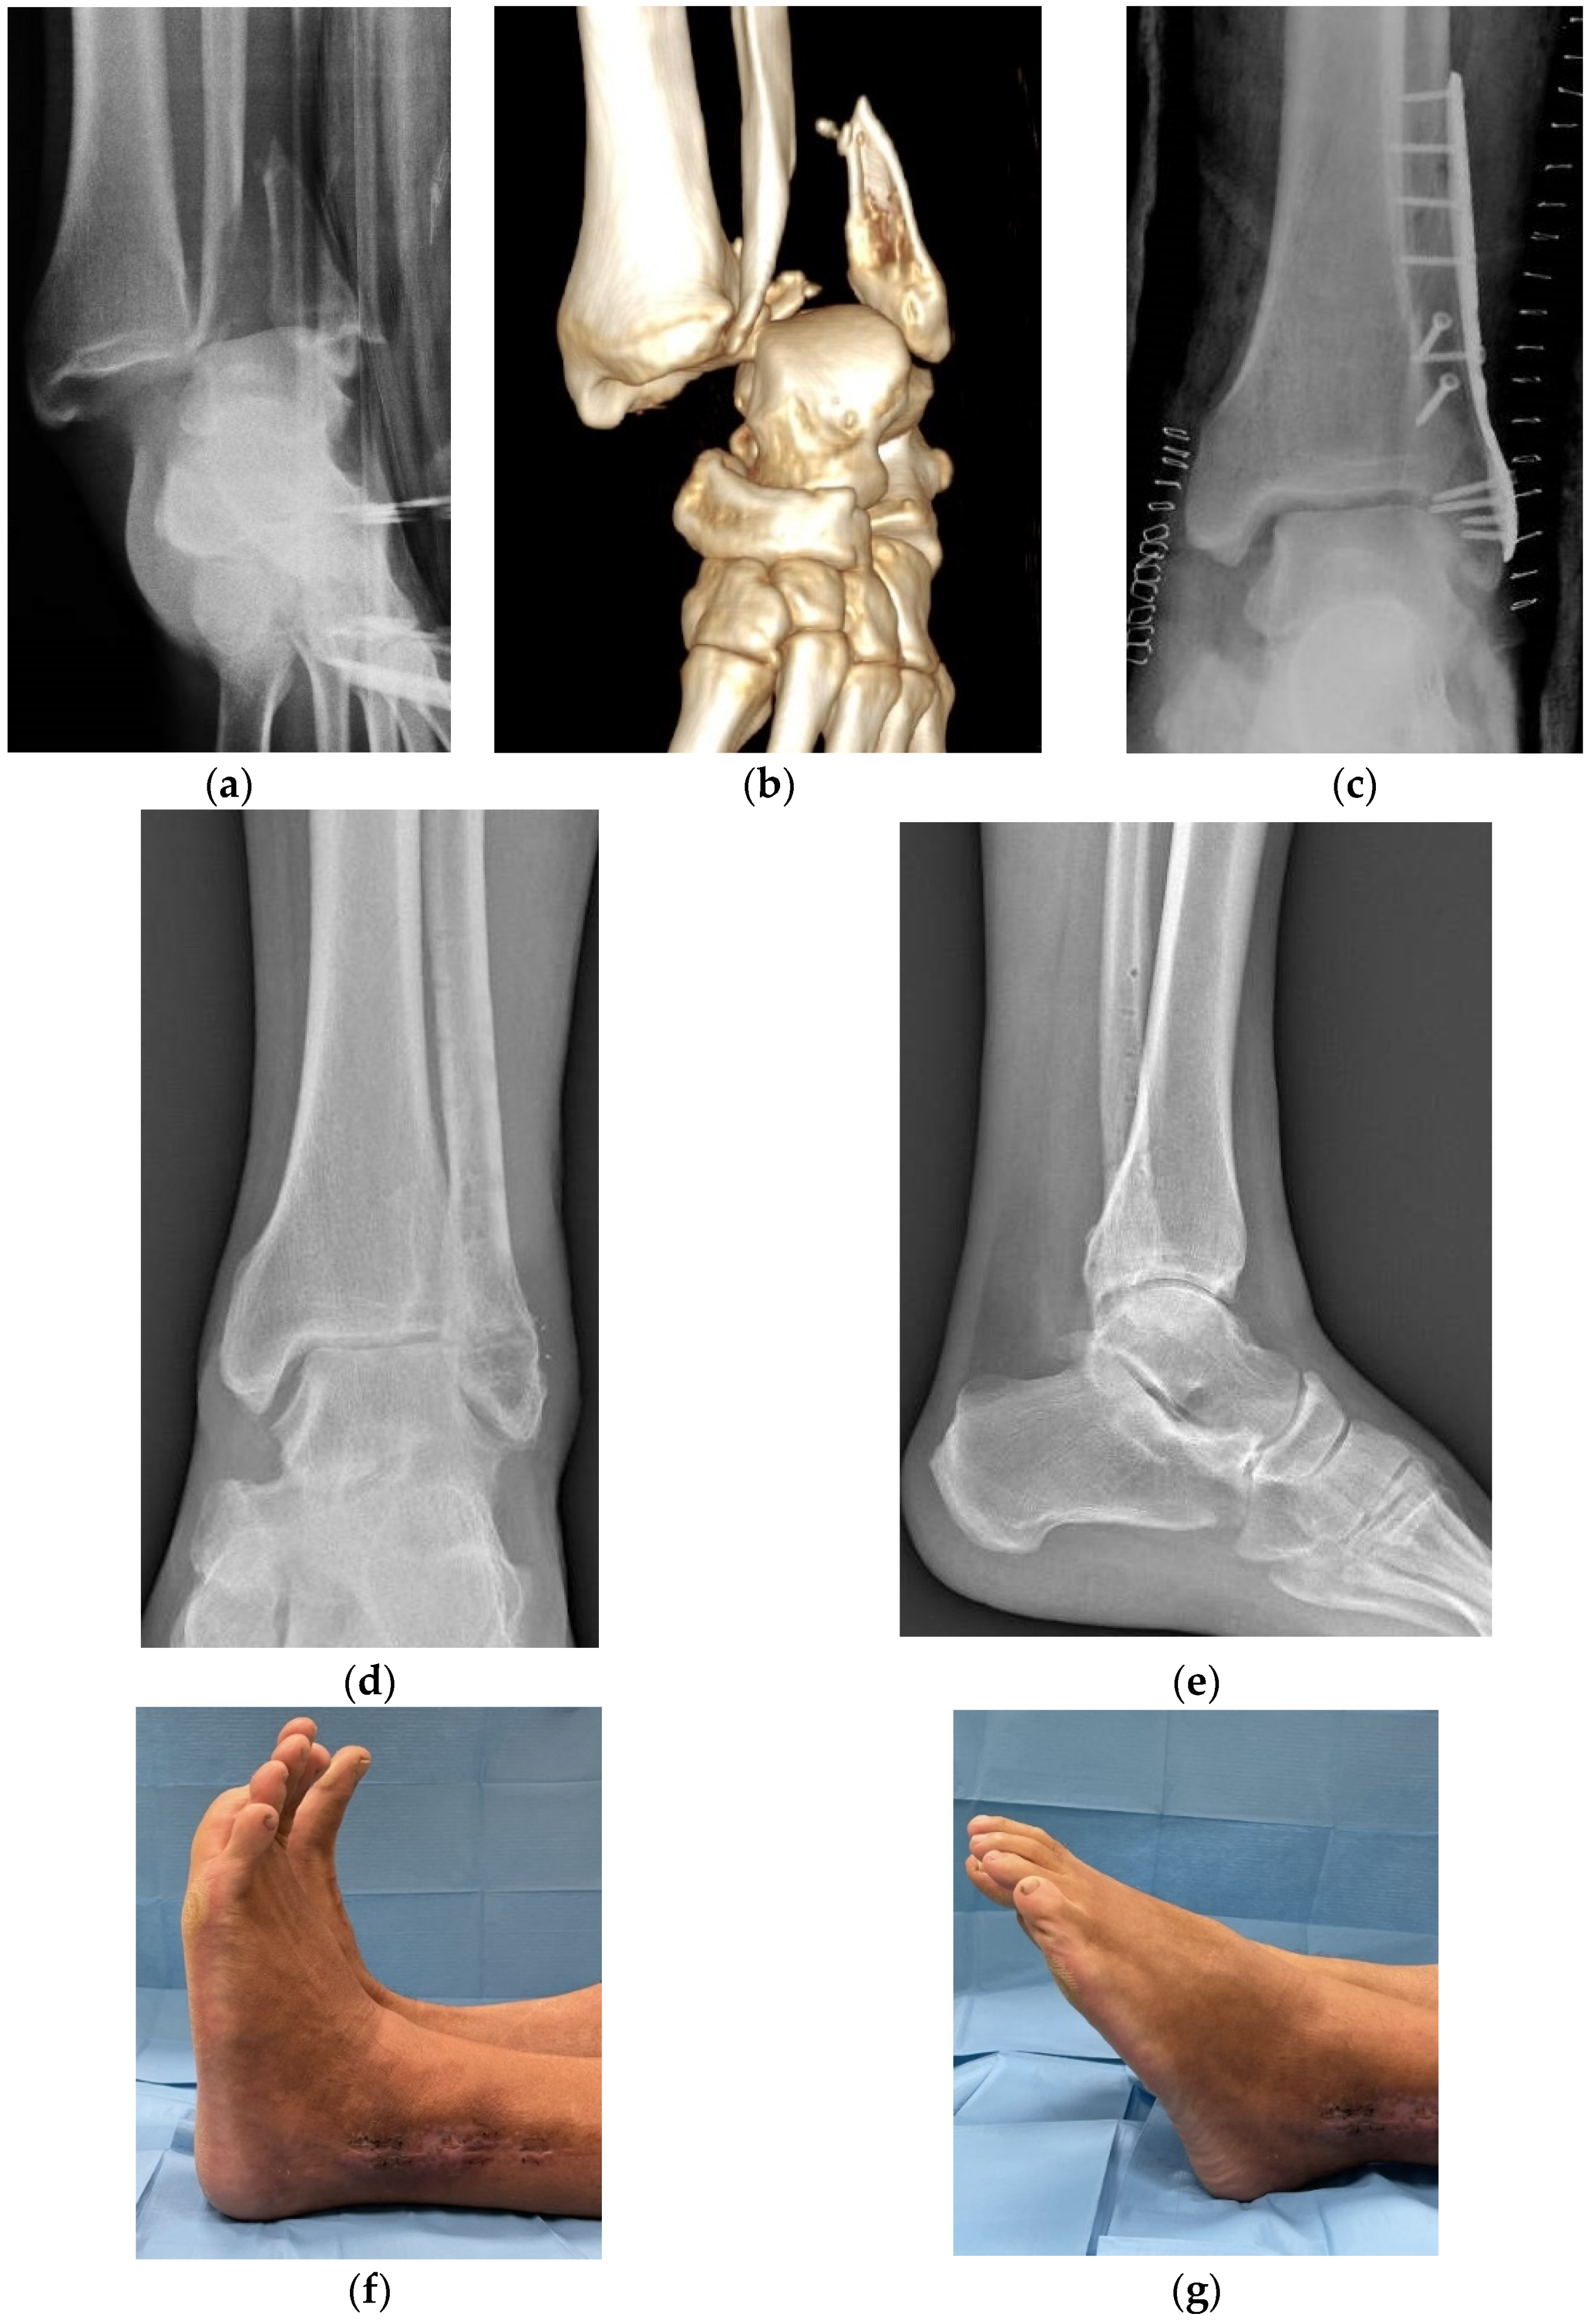

3. Results